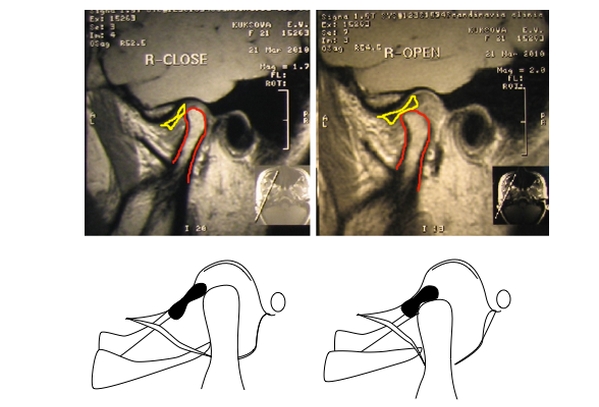

Сканирование занимает около 40–60 минут. Если у пациента есть жалобы на работу челюстей, врач проводит функциональные пробы, прося открыть и закрыть рот, пока аппарат делает необходимые снимки в различных проекциях. Это позволяет наблюдать за работой мышц и суставов в динамике.

Высококачественные снимки позволяют детально рассмотреть даже незначительные изменения в структуре челюстного сустава и отслеживать прогрессирование заболевания.